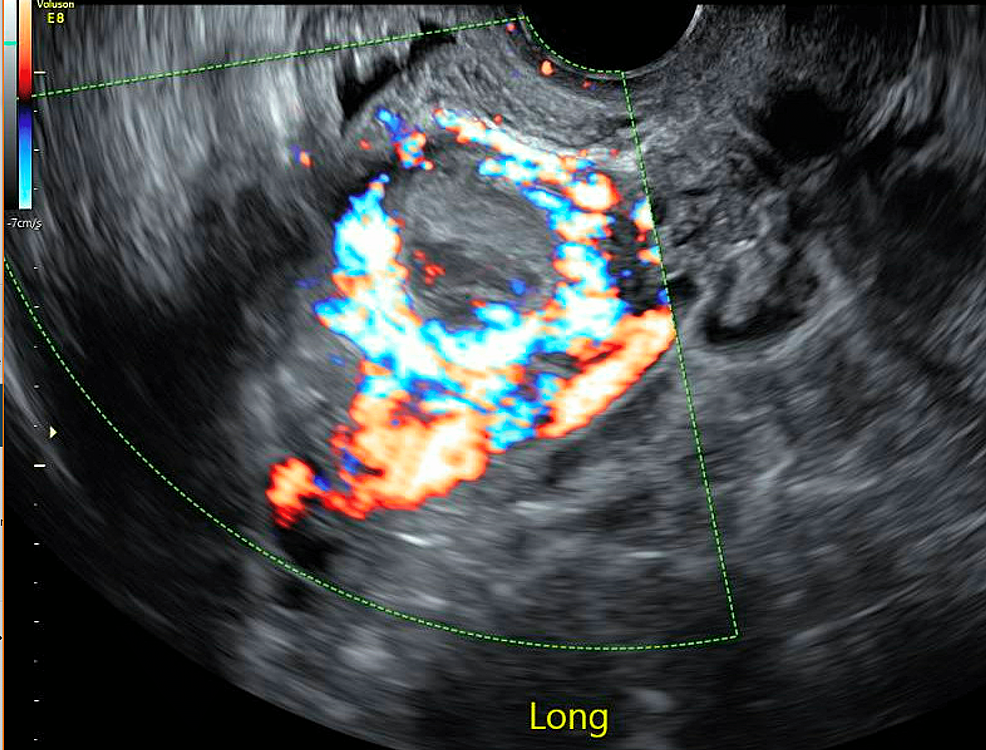

From www.researchgate.net

(PDF) Predicting intraoperative hemorrhage during curettage treatment Scar Healing During Pregnancy Find out how to prevent and manage scar. learn about cesarean scar pregnancy (csp), a rare but serious condition that occurs when a pregnancy implants on. this final stage of healing can last up to a year, during which time your thick, puffy scar tissue flattens and fades in color. Hygiene, pelvic floor exercises and diet are important. Scar Healing During Pregnancy.